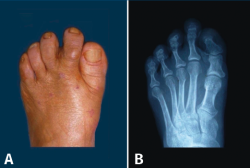

Figura 11. Hallux valgus en una adolescente. A: radiografía del pie de la niña cuando tenía 4 años; B y C: aspecto clínico y radiológico a los 12 años de edad.

R. Miralles y N. A. Barnicot en un estudio llevado a cabo en Mozambique y Nigeria, en poblaciones que habitualmente no llevan ningún tipo de calzado(48,49), no encontraron HV. En Japón, las primeras publicaciones sobre HV aparecen después de la segunda guerra mundial, cuando las mujeres japonesas empiezan a utilizar calzado occidental(50). Recordemos también que existen HV congénitos aislados o que forman parte de una enfermedad generalizada como la fibrodisplasia osificante progresiva(51). En ocasiones, también podemos ver HV juveniles en adolescentes que nunca han llevado calzado estrecho por su parte anterior (Figura 11).